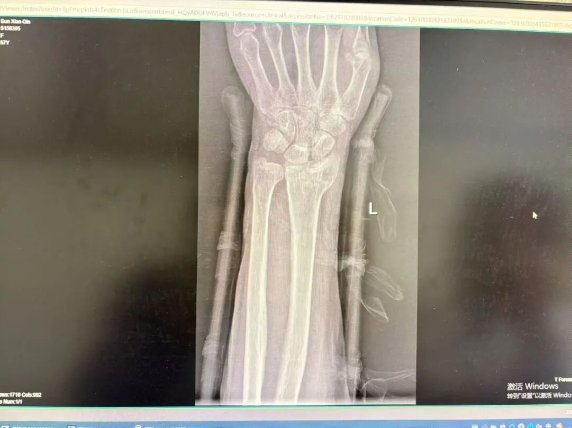

(骨折图示)

如果骨折是稳定的、没有明显移位的(比如青枝骨折),或者经过手法复位后对位良好、非常稳定的—— 我会优先考虑小夹板。 它的“动静结合”理念能让你在康复早期就开始活动,最大程度保留功能,体验感更好,恢复更快。

如果骨折是粉碎的、不稳定的、或者复位后容易再移位的 —— 那我必须请出石膏这位“镇山太保”。 此时,坚固的固定是第一要务,必须先确保骨头在一个良好的位置上长起来。

(石膏X光图示)

(夹板X光图示)